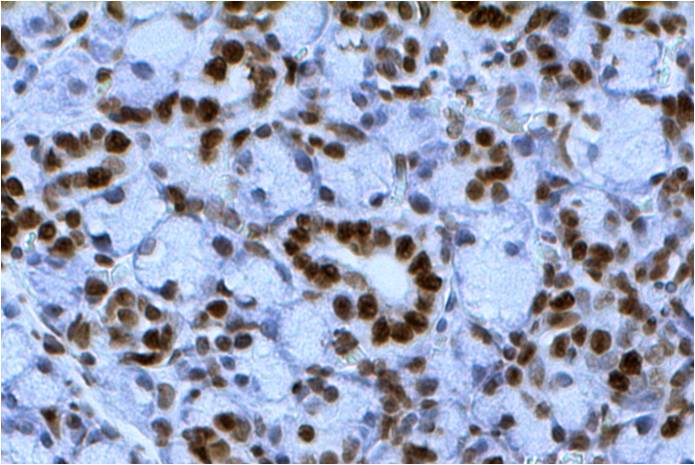

Introduction To order Documents Related products Introduction Internucleosomal cleavage of DNA is a hallmark of apoptosis. DNA cleavage in apoptotic cells can be detected in situ in fixed cells or tissue sections using the terminal deoxynucleotidyl transferase (TdT) mediated dUTP nick-end labeling (TUNEL) method. TUNEL is highly selective for the detection of apoptotic cells but […]

Introduction To order Documents Related products Introduction Internucleosomal cleavage of DNA is a hallmark of apoptosis. DNA cleavage in apoptotic cells can be detected in situ in fixed cells or tissue sections using the terminal deoxynucleotidyl transferase (TdT) mediated dUTP nick-end labeling (TUNEL) method. TUNEL is highly selective for the detection of apoptotic cells but […]